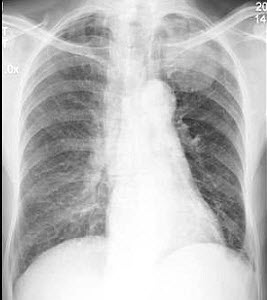

106、单项选择题

男,63岁,痰中带血2天,不发热,X线检查如图所示,最可能的诊断是()

A.左肺上沟瘤

B.左上肺癌

C.左肺炎性假瘤

D.左肺结核瘤

E.左肺错构瘤